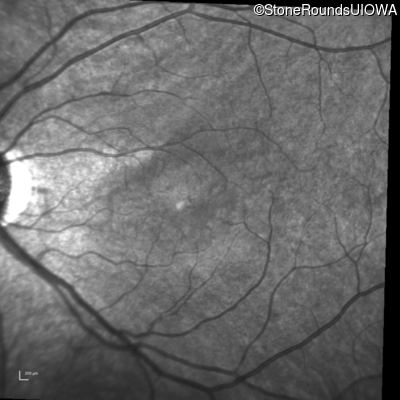

Infrared Fundus Photograph - Left - 20/50

Exemplar